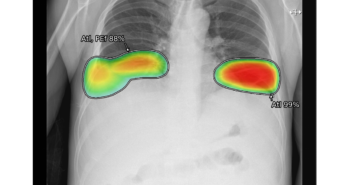

의료 인공지능(AI) 기업 루닛이 최근 필리핀 마닐라 소재 빅토리아노 루나 메디컬센터(Victoriano Luna Medical Center) 군병원과 제너럴 티니오(General Tinio)시 지역 보건소에 흉부 엑스레이 AI 영상분석 솔루션 '루닛 인사이트 CXR'을 설치 완료했다. 이는 루닛 AI 솔루션을 해외 군병원 및 보건소에 도입한 첫번째 사례로, 과학기술정보통신부 및 정보통신산업진흥원(NIPA)이 추진하는 'AI 융합 의료영상 진료판독시스템 사업'을 통해 진행됐다. 루닛은 필리핀 빅토리아노 루나 메디컬센터 군병원과 지역 보건소에 이동 설치 가능한 이동형 엑스레이 장비 타입의 AI 솔루션을 설치했으며, 이를 통해 10가지 흉부 질환을 검출하고 결핵을 선별할 예정이다. 서범석 루닛 대표는 "루닛은 국내 육해공군 거점병원과 사단 의무대 등 다양한 환경에서 군 의료에 특화된 제품에 대한 검증 작업을 성공적으로 마쳤다"며 "이번 필리핀 군병원 제품 공급을 계기로 해외 군 의료기관으로 사업영역을 넓혀나갈 것"이라고 말했다. 관련 기사 더보기 https://www.venturesquare.net/900704